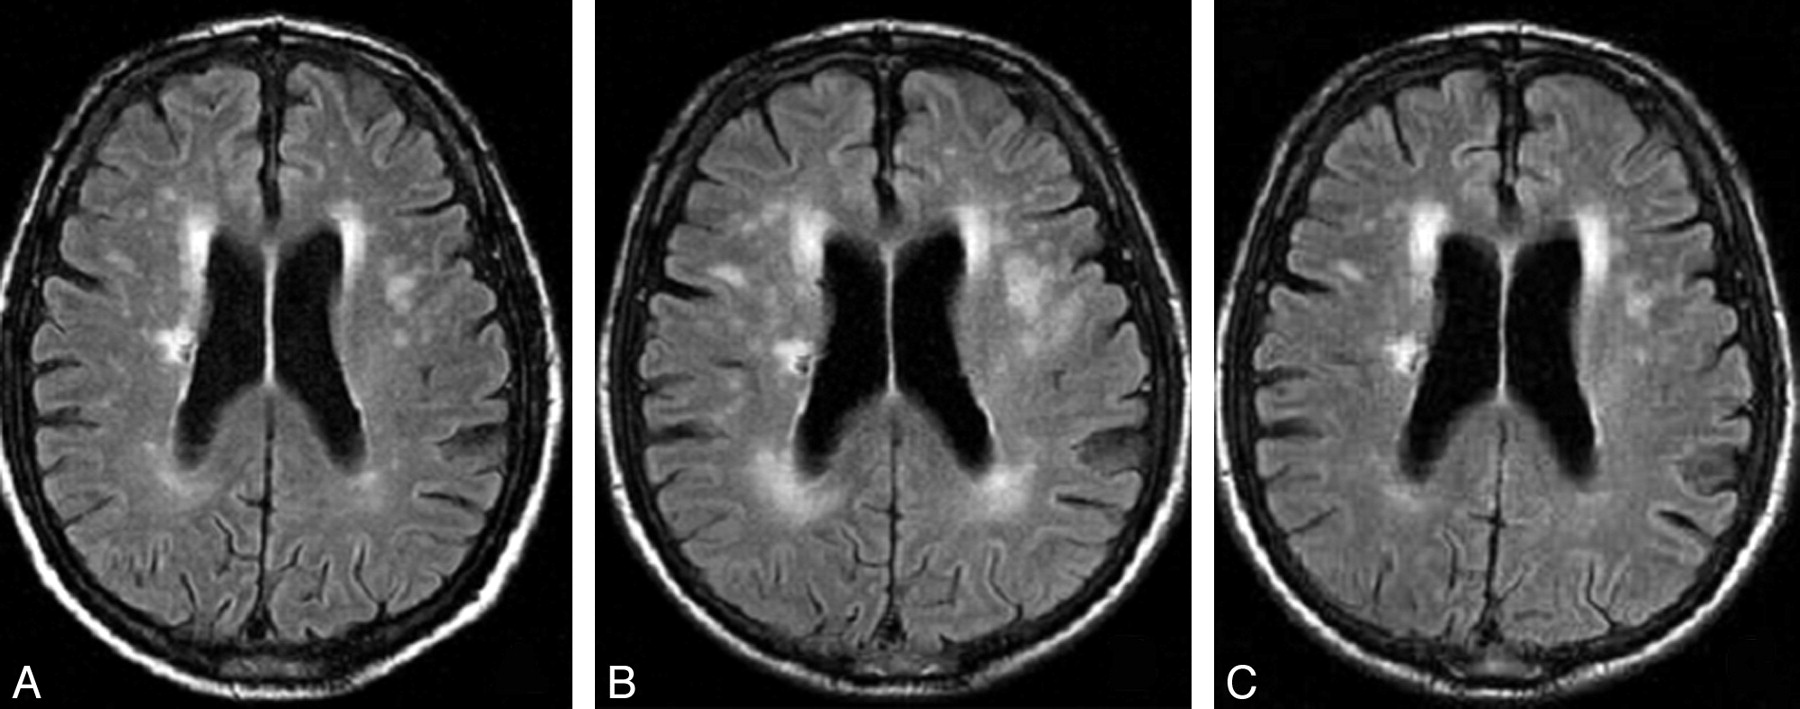

Fazekas grades. Лейкоареоз головного мозга мрт. Перивентрикулярный лейкоареоз мрт. Лейкоареоз Фазекас. Лейкоареоз на кт.

Fazekas grades. Лейкоареоз головного мозга мрт. Перивентрикулярный лейкоареоз мрт. Лейкоареоз Фазекас. Лейкоареоз на кт.

Fazekas grades. Лейкоареоз головного мозга мрт. Перивентрикулярный лейкоареоз мрт. Перивентрикулярный лейкоареоз головного мозга на кт. Лейкоареоз Fazekas 1 что это.

Fazekas grades. Лейкоареоз головного мозга мрт. Перивентрикулярный лейкоареоз мрт. Перивентрикулярный лейкоареоз головного мозга на кт. Лейкоареоз Fazekas 1 что это.

Fazekas grades. Лейкоареоз на кт. Лейкоареоз головного мозга мрт. Перивентрикулярный лейкоареоз. Перивентрикулярный лейкоареоз мрт.

Fazekas grades. Лейкоареоз на кт. Лейкоареоз головного мозга мрт. Перивентрикулярный лейкоареоз. Перивентрикулярный лейкоареоз мрт.